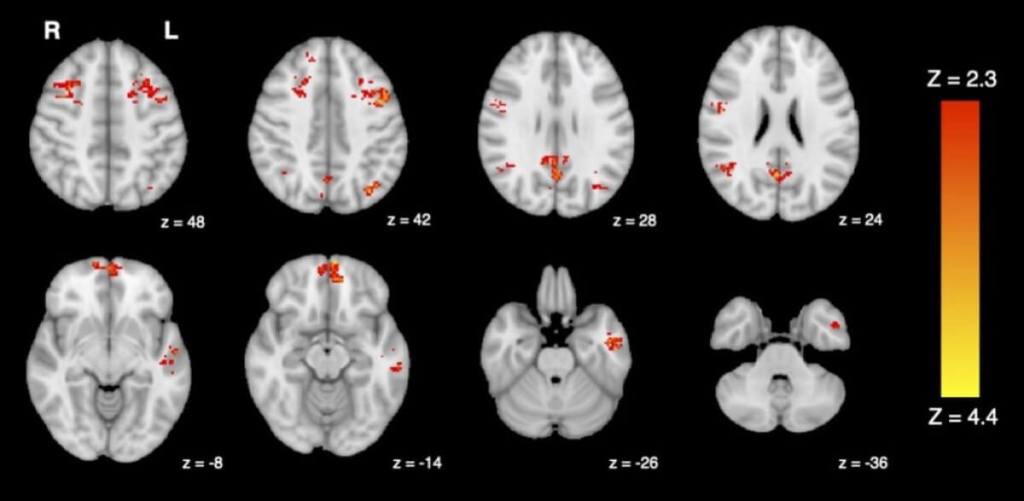

The team briefly exposed 25 healthy adults to either diesel exhaust or filtered air in a lab. They used functional magnetic resonance imaging (fMRI) to measure their brain activity before and after each exposure. One of the areas they looked at for possible changes is the brain’s default mode network (DMN). The DMN includes several brain regions connected together that play a part in people’s internal thoughts and memories. The fMRI scans show that people exposed to diesel exhaust have lower DMN activity compared to the air-filtered group.

“We know that altered functional connectivity in the DMN has been associated with reduced cognitive performance and symptoms of depression, so it’s concerning to see traffic pollution interrupting these same networks,” explains study first author Jodie Gawryluk, a psychology professor at the University of Victoria. “While more research is needed to fully understand the functional impacts of these changes, it’s possible that they may impair people’s thinking or ability to work.”

fMRI shows decreased functional connectivity in the brain following exposure to traffic pollution. (Credit: University of British Columbia)